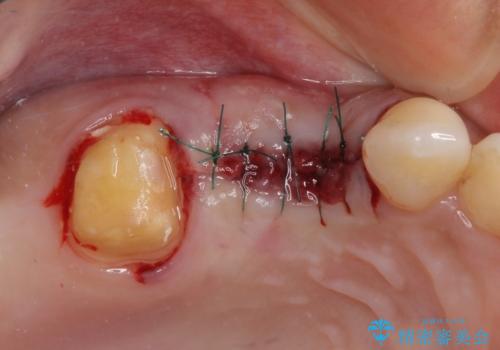

レントゲン写真などで診査した結果、奥歯の銀歯の下にはむし歯が多く存在し、右上の奥歯は歯根が破折していました。

破折した歯を抜去し、インプラントによる補綴を行うこととしました。